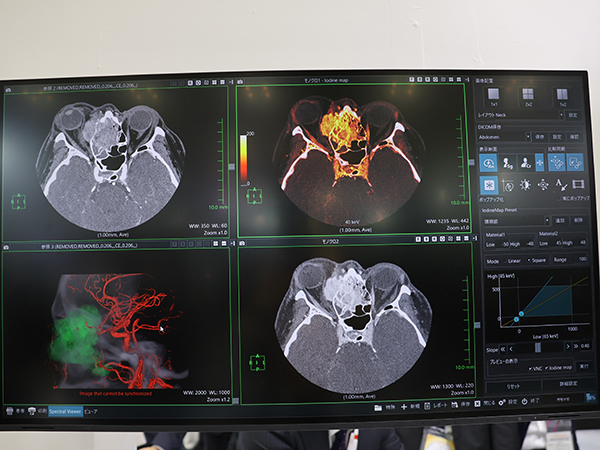

ブースでは,医用画像解析3Dワークステーション「Abierto Vision」や読影支援ソリューション「Abierto Reading Support Solution(Abierto RSS)」,医療情報統合ビューア「Abierto Cockpit」,「Abierto PACS」など多様なAbiertoシリーズのラインアップが展示された。このうち,AIを活用した自動化技術や多彩な解析アプリケーションで画像解析ワークフローを支援するAbierto Visionは,Ultimionの発売に合わせて「Spectral Viewer」が新たにリリースされた。Spectral Viewerは,基準物質データから仮想単色X線画像やヨードマップを作成し,1画面で撮影画像とあわせて参照することができるもので,診療放射線技師がワークステーションとして,また放射線科医が読影ビューワとして活用できる。過去画像との比較やVR画像に加え,ヨードマップ,任意keV画像などのスペクトラル画像を一覧でき,より多くの情報を閲覧しながらの効率的な読影を支援する。Abierto Vision の特長である直感的な操作性がSpectral Viewerにも生かされており,keV変更はスロープの傾きをグラフで確認しながらスライダーバーで容易に調整が可能である。調整結果の画像がリアルタイムに表示されることから,読影に適した任意のkeV画像を医師自身で得ることができる。

Ultimionの発売に合わせてリリースされた「Abierto Vision」の「Spectral Viewer」